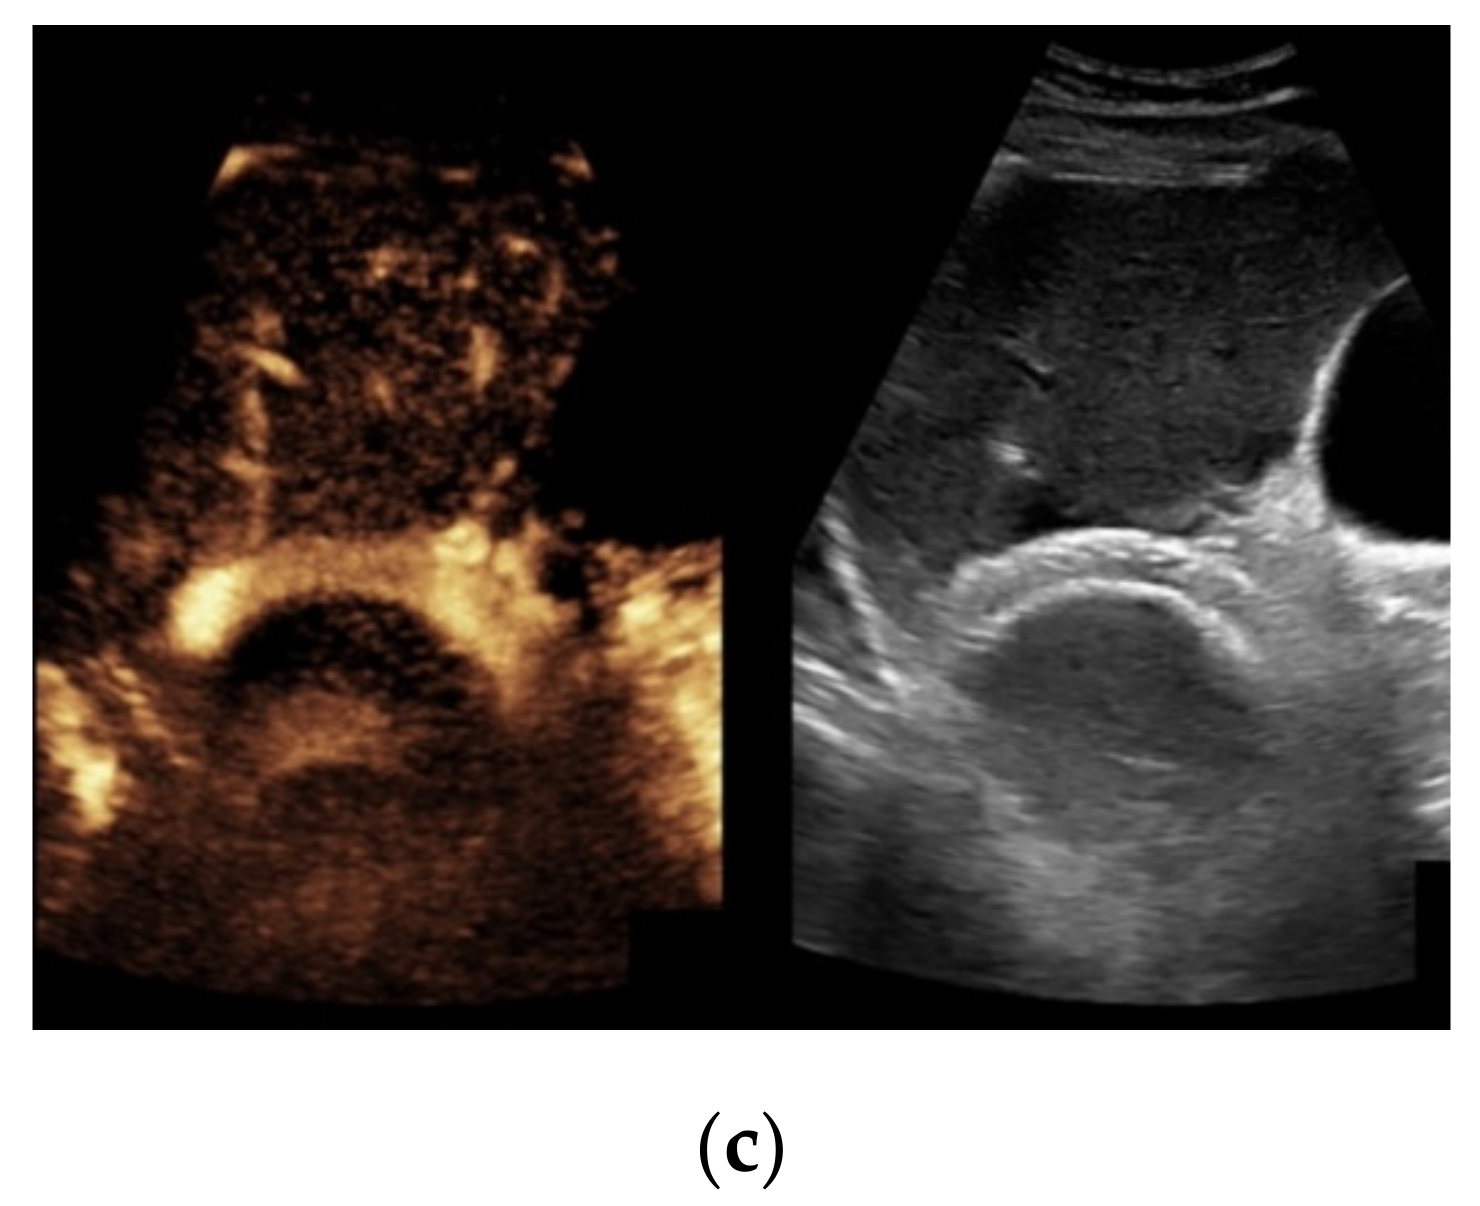

When taking a closer look at the results of the CEUS examinations, 70.8% (n = 75) of the patients showed regular stent perfusion (Figure 4), 17.9% (n = 19) of the patients featured TIPS occlusion (Figure 5) while 6.6% (n = 7) patients had stent thrombosis (Figure 6). In contrast to the results from CDUS, there were no patients with only partial accessibility of the TIPS during CEUS, while the two patients with meteorism also were not assessable during CEUS. The three patients categorized in “others” showed simultaneous findings between CDUS and CEUS (Table 2).

Considering findings from CDUS and CEUS examination, in eight patients results were inconsistent (7.6%). Five patients who were only partially assessed via Color Doppler ultrasound showed a regular perfusion by using CEUS (Figure 7), two patients in whom inconspicuous TIPS perfusion was registered by CDUS showed partial occluding stent thrombosis by CEUS while in one patient suspected stent thrombosis in CDUS could not be verified by CEUS (Table 3).

Figure 4. Same patient as in Figure 1 with continuous flow within the transjugular intrahepatic portosystemic shunt (TIPS) without thrombosis or occlusion using microflow imaging (a) and after administration of contrast agent (b,c).

Figure 5. Same patient as in Figure 2. After administration of intravenous contrast, no intraluminal microbubbles can be registered within the transjugular intrahepatic portosystemic shunt compatible with complete occlusion (a,b).

Figure 6. Same patient as in Figure 3. Contrast-enhanced ultrasound shows partial flow signal within the transjugular intrahepatic portosystemic shunt with marginal hypoechoic areas within the stent indicating thrombotic depositions.

Figure 7. 52-year-old female patient with irregular presentation of the transjugular intrahepatic portosystemic shunt (TIPS) on B-mode ultrasound (a) and partial flow on Color Doppler ultrasound (CDUS) (b). After contrast administration, in contrast to CDUS, regular and continuous contrast of the TIPS is seen without evidence of thrombotic alterations or occlusion (c).